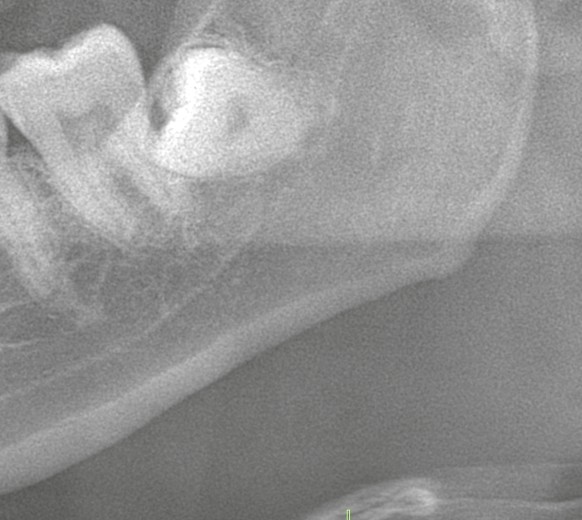

・親知らずの抜歯

歯科での外科処置、特に親知らずの抜歯やインプラント手術は、患者さんにとって大きな緊張を伴う治療です。局所麻酔の注射を行う際や処置の最中に、体が急に反応してしまい、血圧や脈拍が低下し、顔が青白くなったり、意識が遠のいたりすることがあります。これは「迷走神経反射」と呼ばれる現象で、歯科医療の現場では比較的よく見られる合併症のひとつです。